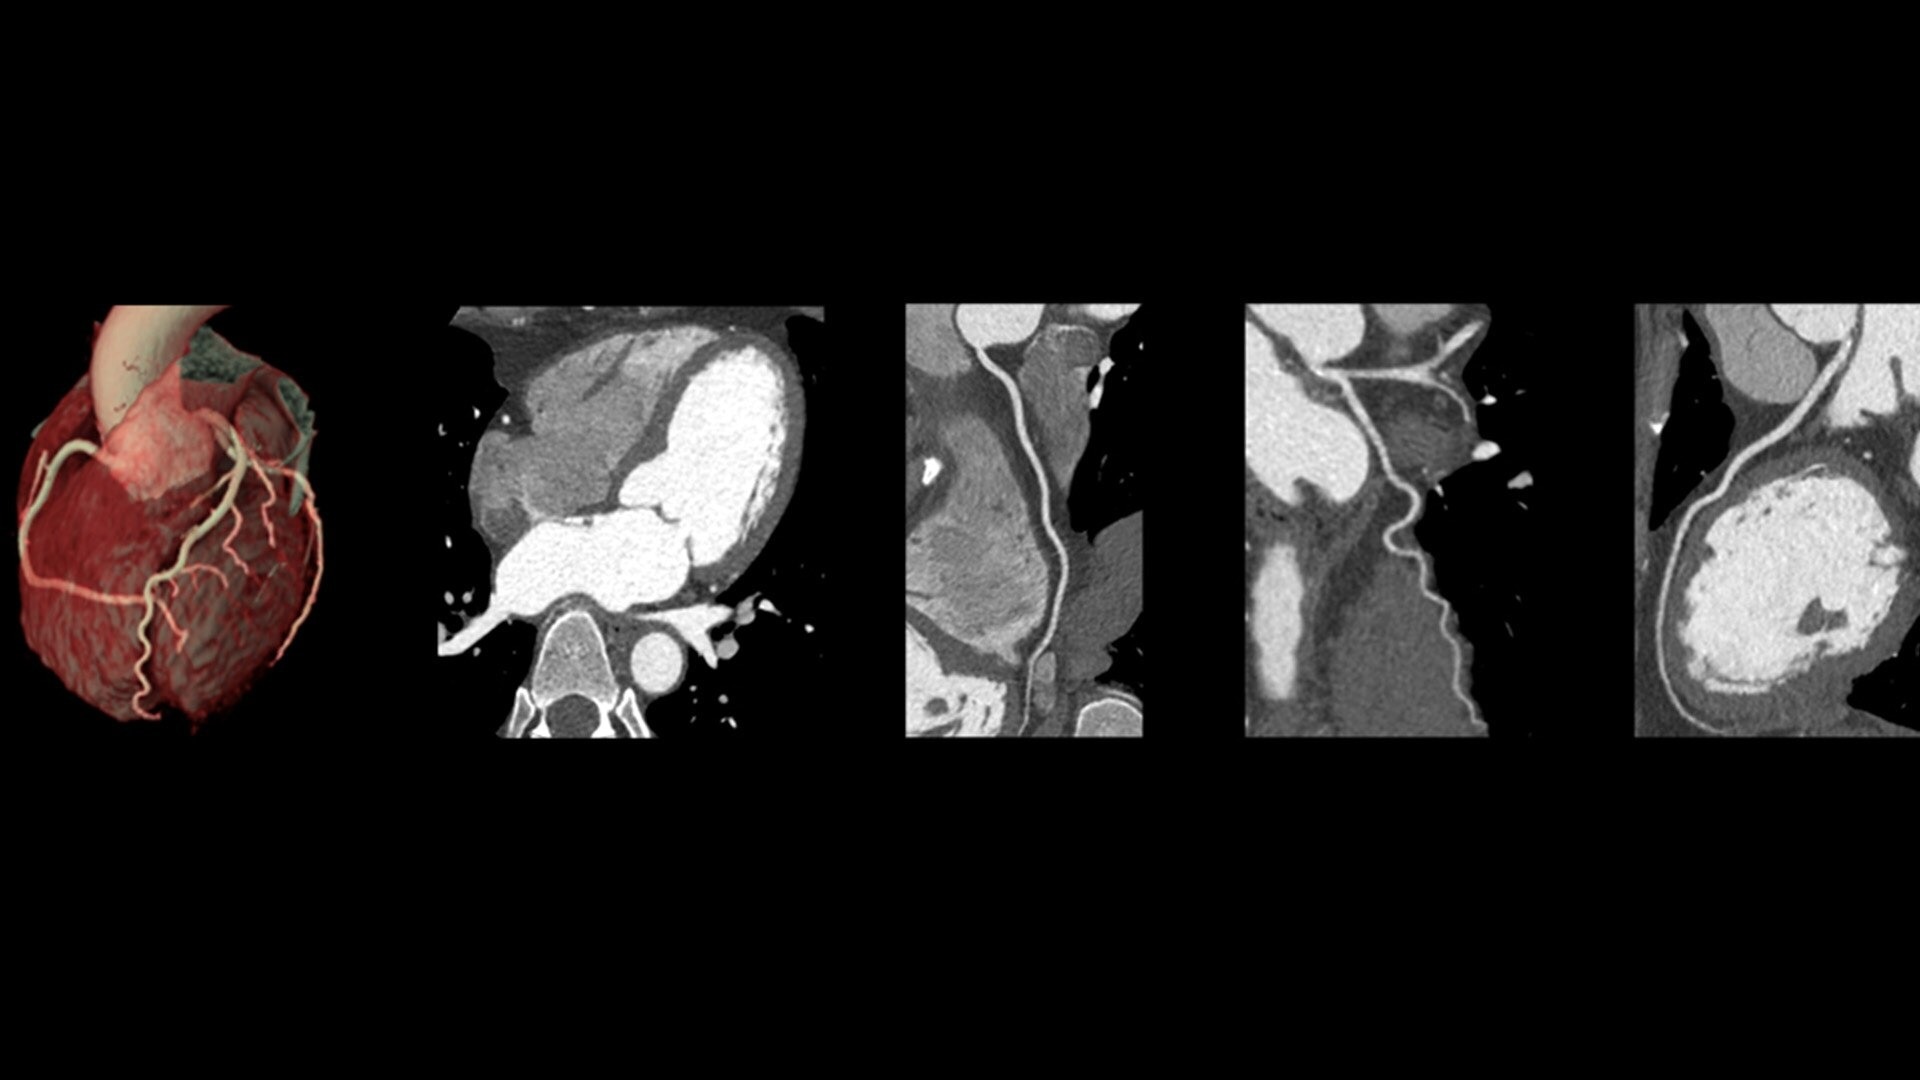

The ECG-less CT (a cardiac CT scan without an ECG trace) is an industry-first

Increases Cardiac CT access

Address cardiac exams where patient access and speed need to be prioritized

Simplified workflow

Useful in exams where excluding ECG traces would streamline patient preparation